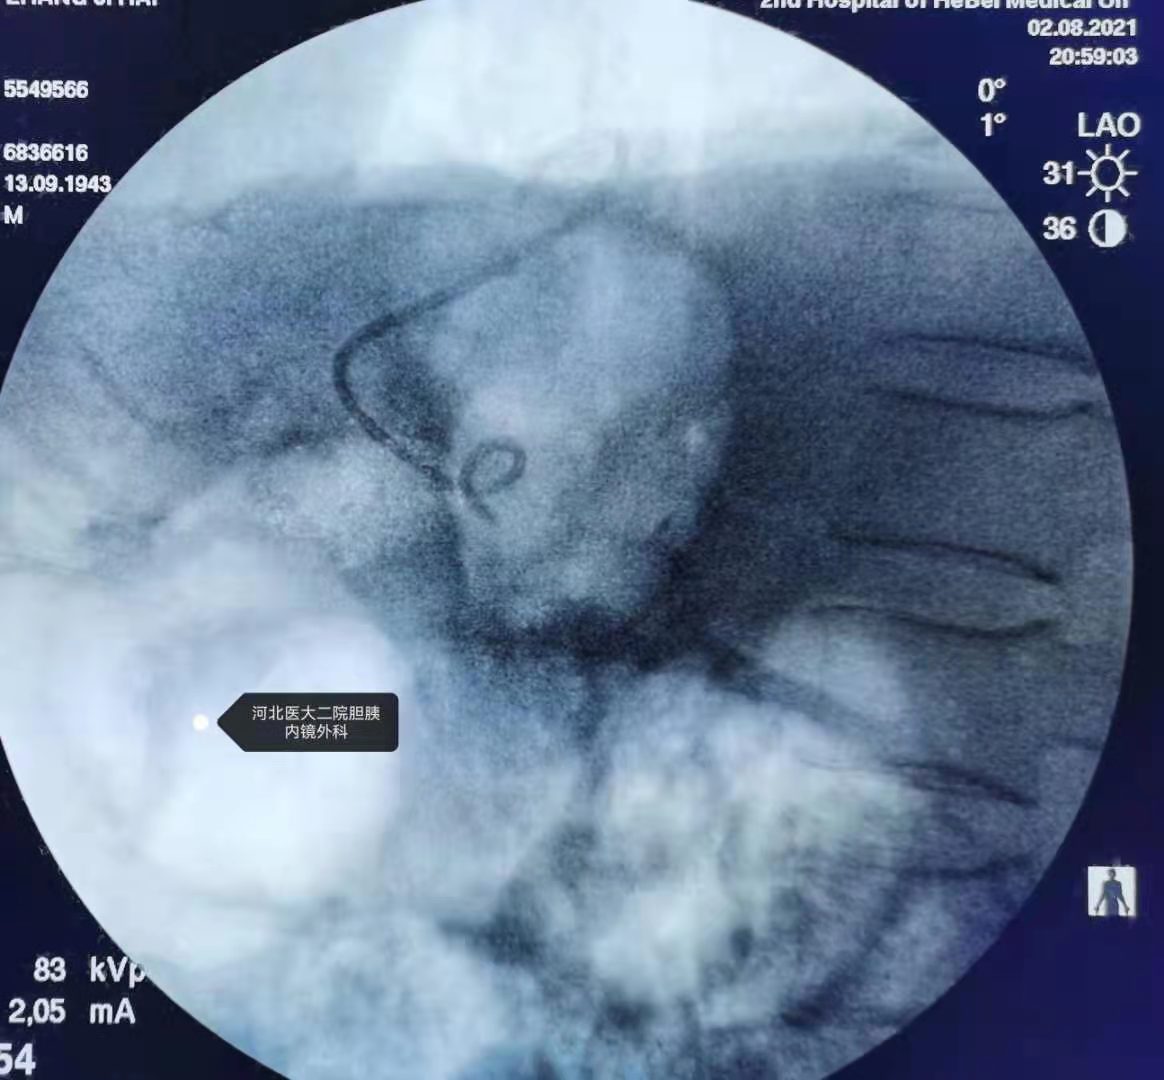

穿刺造影,胆管很细。